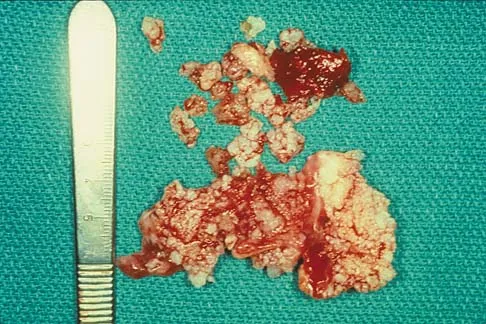

A 16-year-old boy has had thigh pain for the past several months. He denies any history of trauma. Examination reveals a large, deeply fixed, soft-tissue mass in the thigh. Laboratory results show an elevated erythrocyte sedimentation rate (ESR) and leukocytosis. A plain radiograph and MRI scan are shown in Figures 1a and 1b. Biopsy specimens are shown in Figures 1c and 1d. What is the most likely diagnosis?